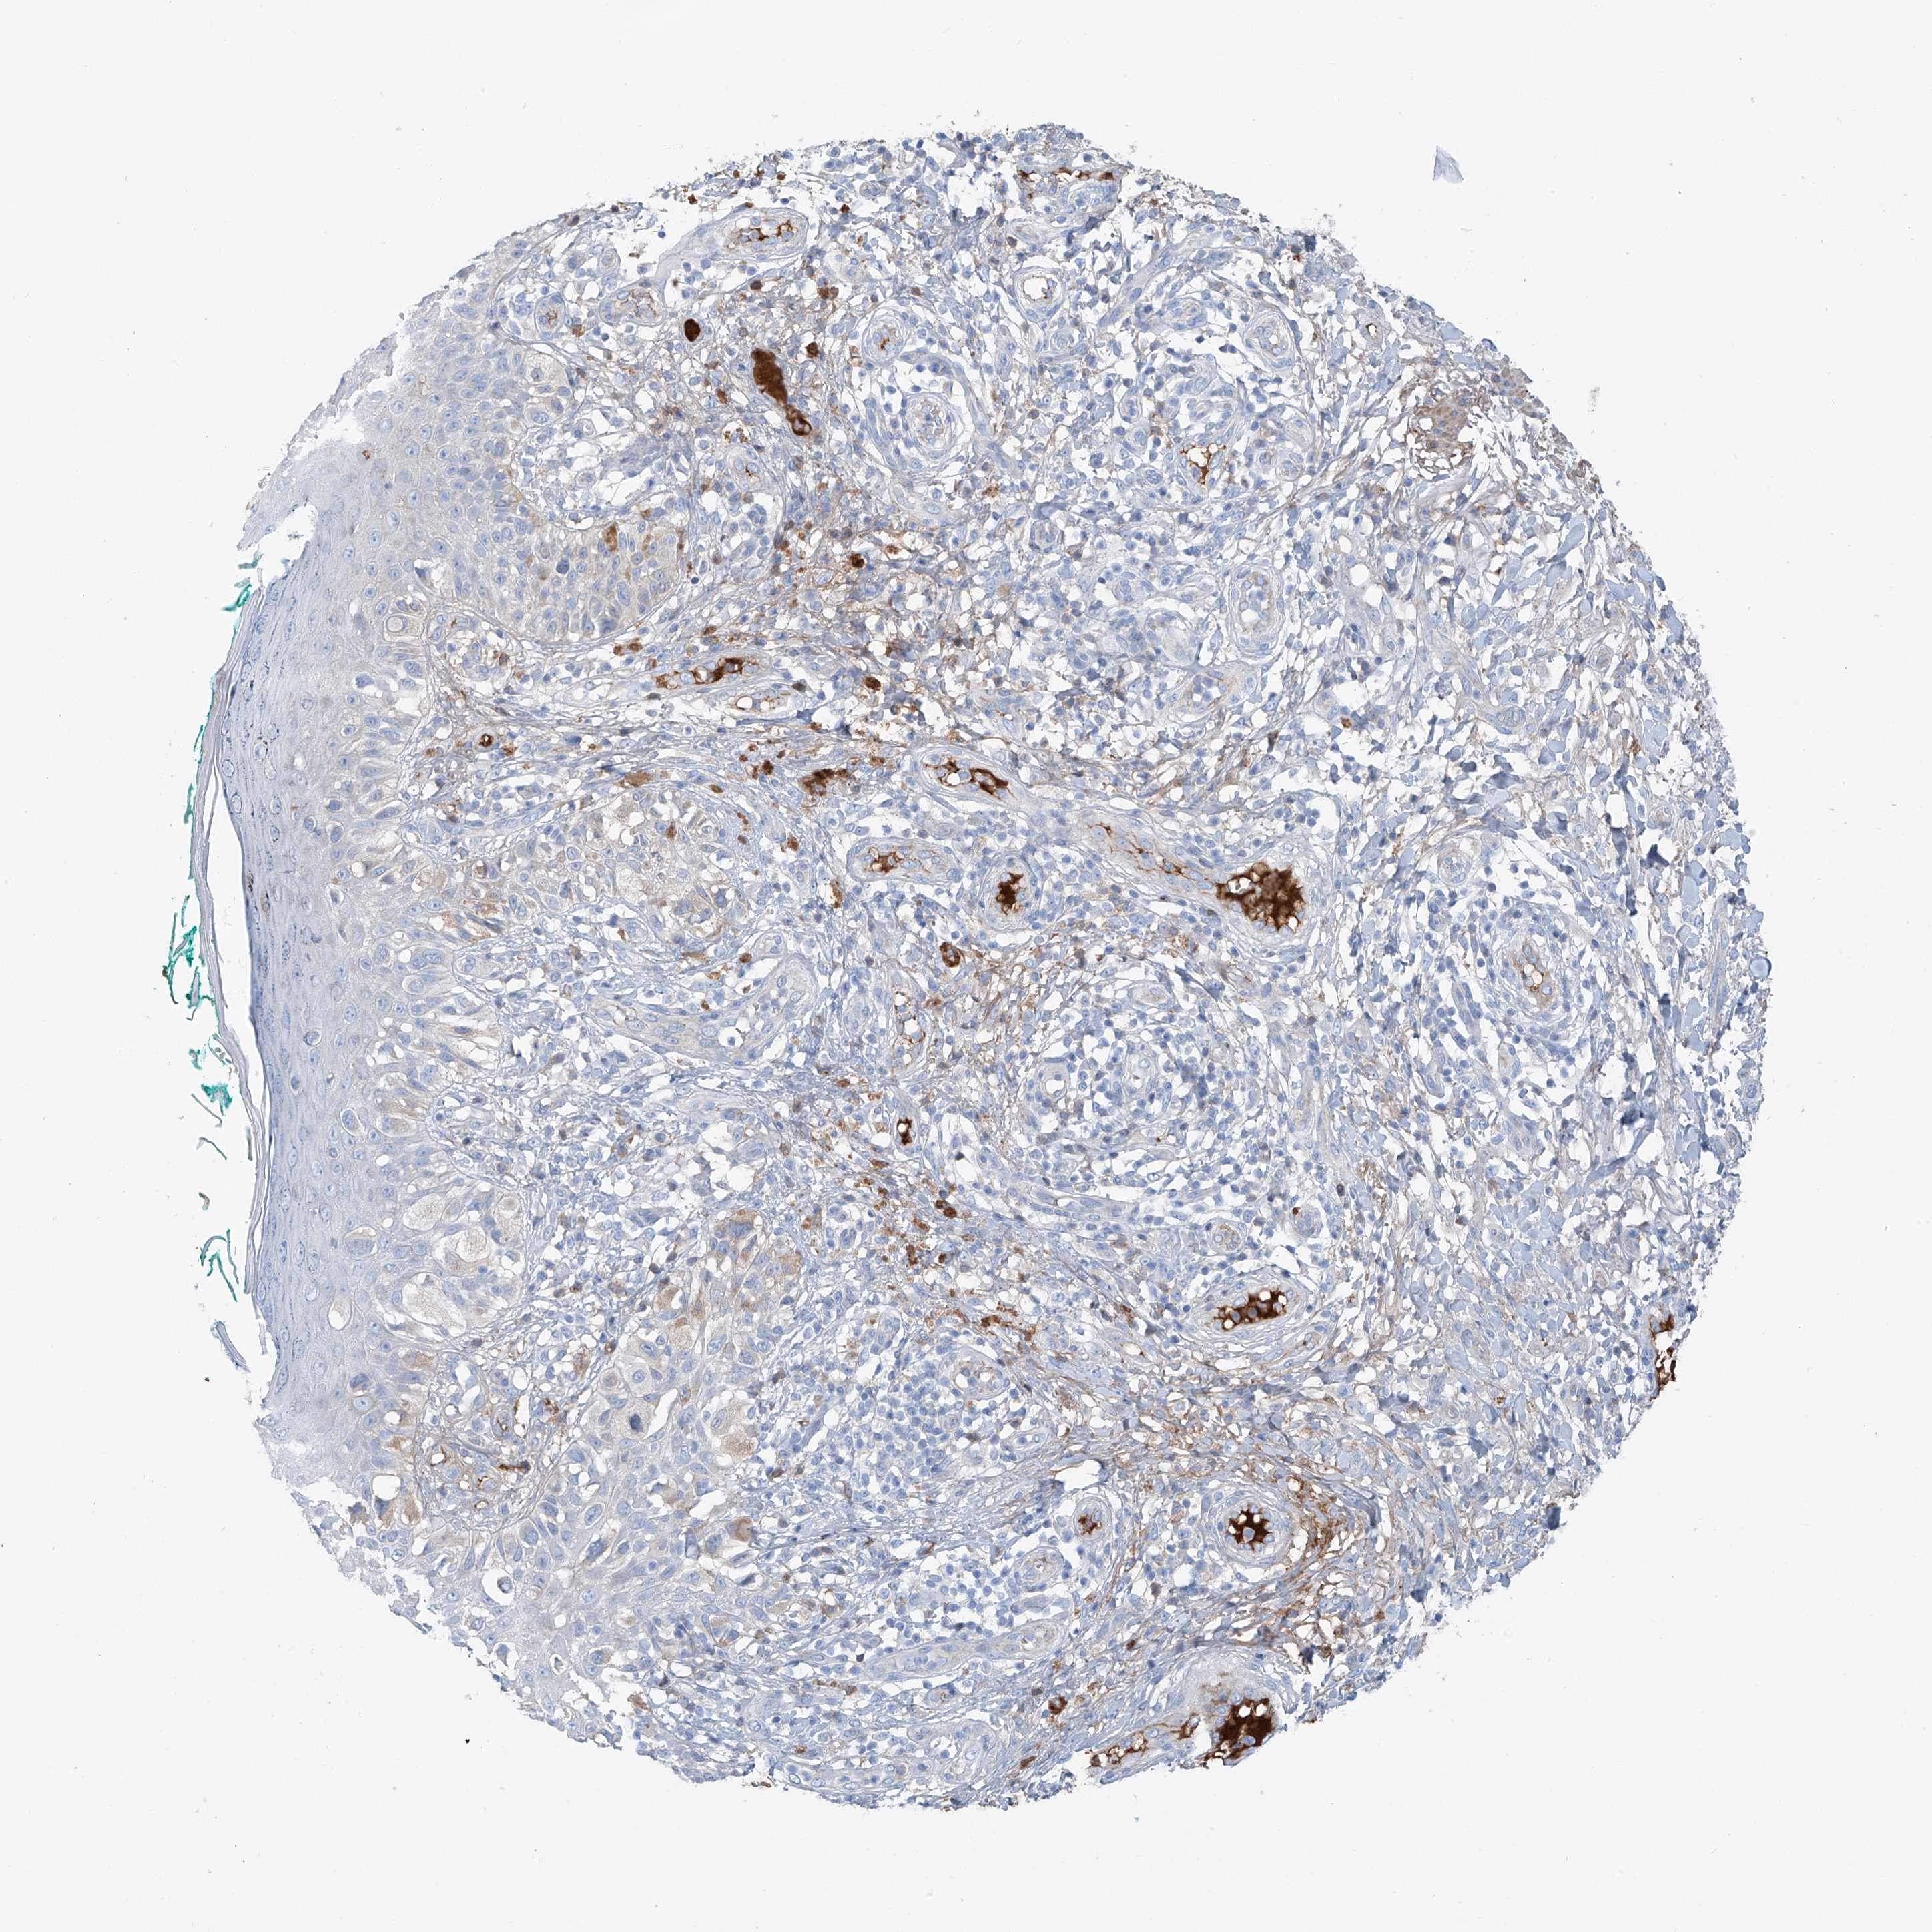

MELANOMA - Protein expressioni

A mouse-over function shows sample information and annotation data. Click on an image to view it in a full screen mode. Samples can be filtered based on level of antibody staining by selecting one or several of the following categories: high, medium, low and not detected. The assay and annotation is described here.

Note that samples used for immunohistochemistry by the Human Protein Atlas do not correspond to samples in the TCGA dataset.

Antibody stainingi

Antibody staining in the annotated cell types in the current human tissue is reported as not detected, low, medium, or high, based on conventional immunohistochemistry profiling in selected tissues. This score is based on the combination of the staining intensity and fraction of stained cells.

Each image is clickable and will lead to virtual microscopy that enables deeper exploration of all samples and also displays staining intensity scores, fraction scores and subcellular localization as well as patient and tissue information for each sample.

Antibody HPA009134

Staining

High

Medium

Low

Not detected

Intensity

Strong

Moderate

Weak

Negative

Quantity

>75%

75%-25%

<25%

None

Location

Nuclear

Cytoplasmic/membranous

Cytoplasmic/membranous,nuclear

Malignant melanoma, NOS

Malignant melanoma, Metastatic site